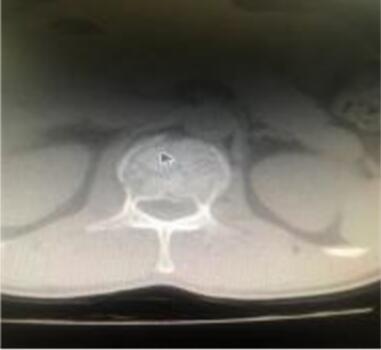

患者趙某,48歲,因高處摔傷致腰背部疼痛伴下肢活動受限于7月8日入院,患者入院時下肢肌力4級,小便解出困難,鞍區(qū)感覺障礙,由120急救車送到我院,脊柱外科立馬組織人員接診,開通檢查綠色通道,完善腰椎CT、MRI后,患者診斷為腰1、3椎體爆裂性骨折,如不及時實施手術隨時都有神經癥狀進一步加重的風險,甚至癱瘓。

術前CT及MRI